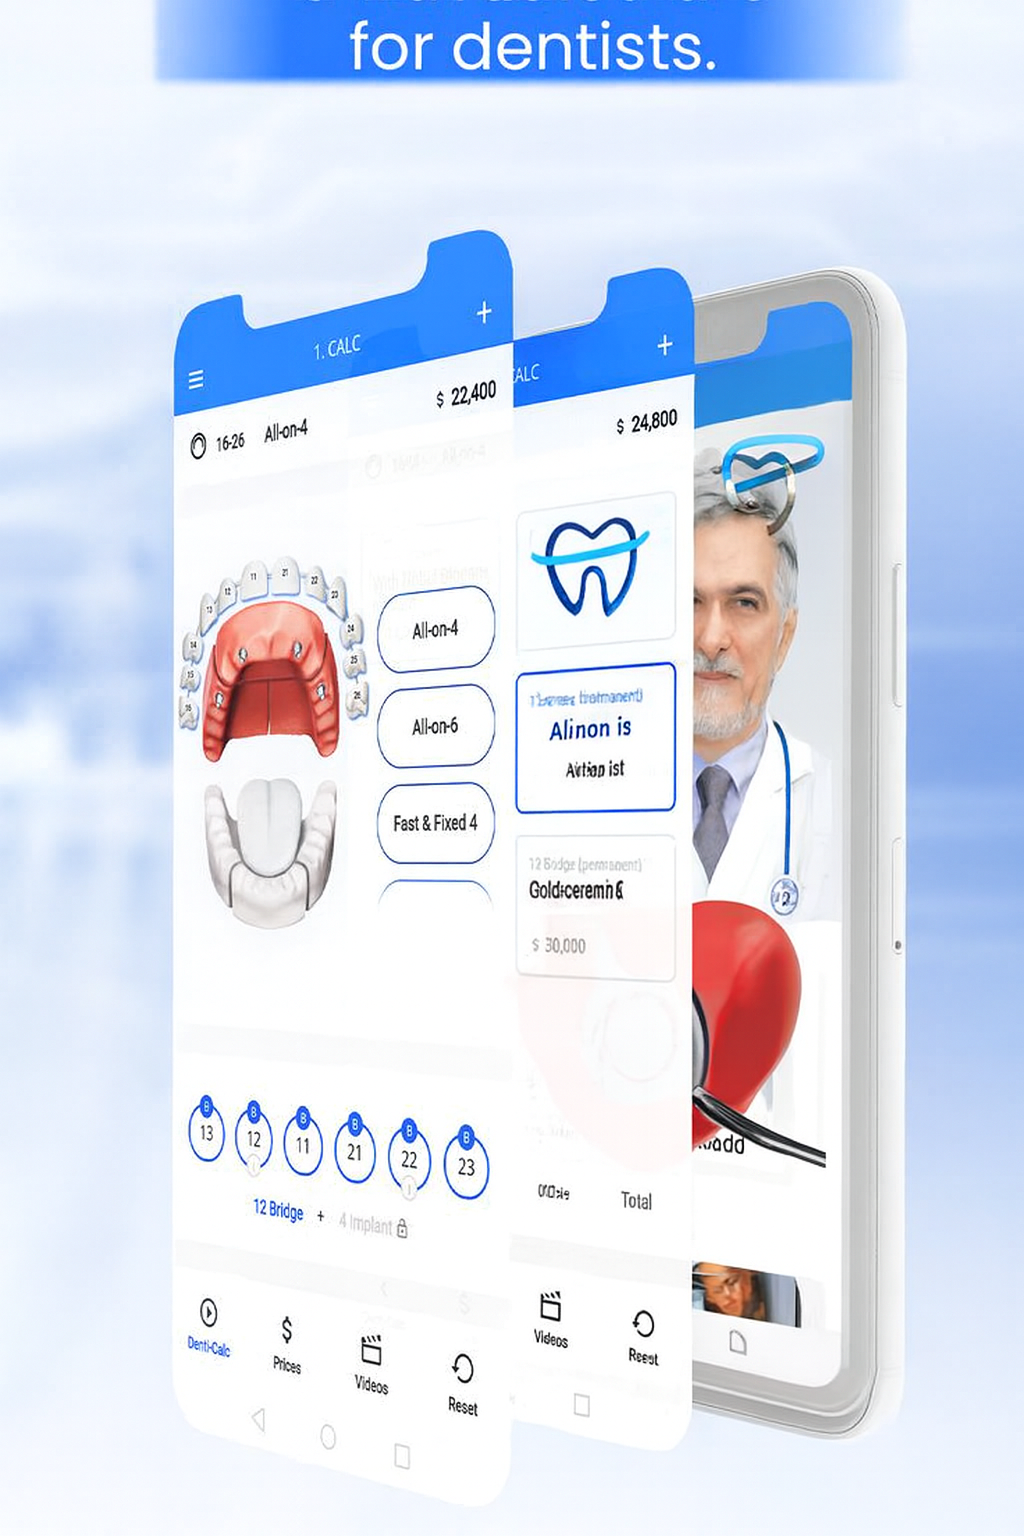

Transform the way you manage your health with Doctor Finder, the ultimate doctor consultation app designed to bring top-notch medical care to your fingertips.

Process

Appointment Process

Search Best Online Doctors

View Doctor Profile